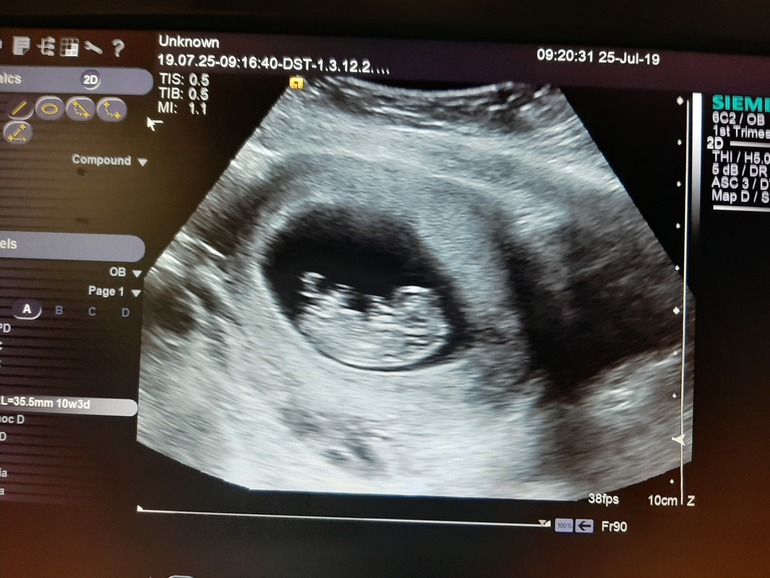

У нас получилось! Я беременна!Добрый день, сдала сегодня ЭКГ, кровь и была на скрининге... врач через 3 секунды говорит, тут совсем малыш, приходите 8 августа, у вас не верно срок поставили... главное сердце у малютки бьется хорошо, а то что ошиблись со сроком не критично... может, у кого то были похожие случаи? Поделитесь пожалуйста

Скриннинг проводят при ктр не менее 45 мм.

Скорее всего у вас по Узи он был меньше.